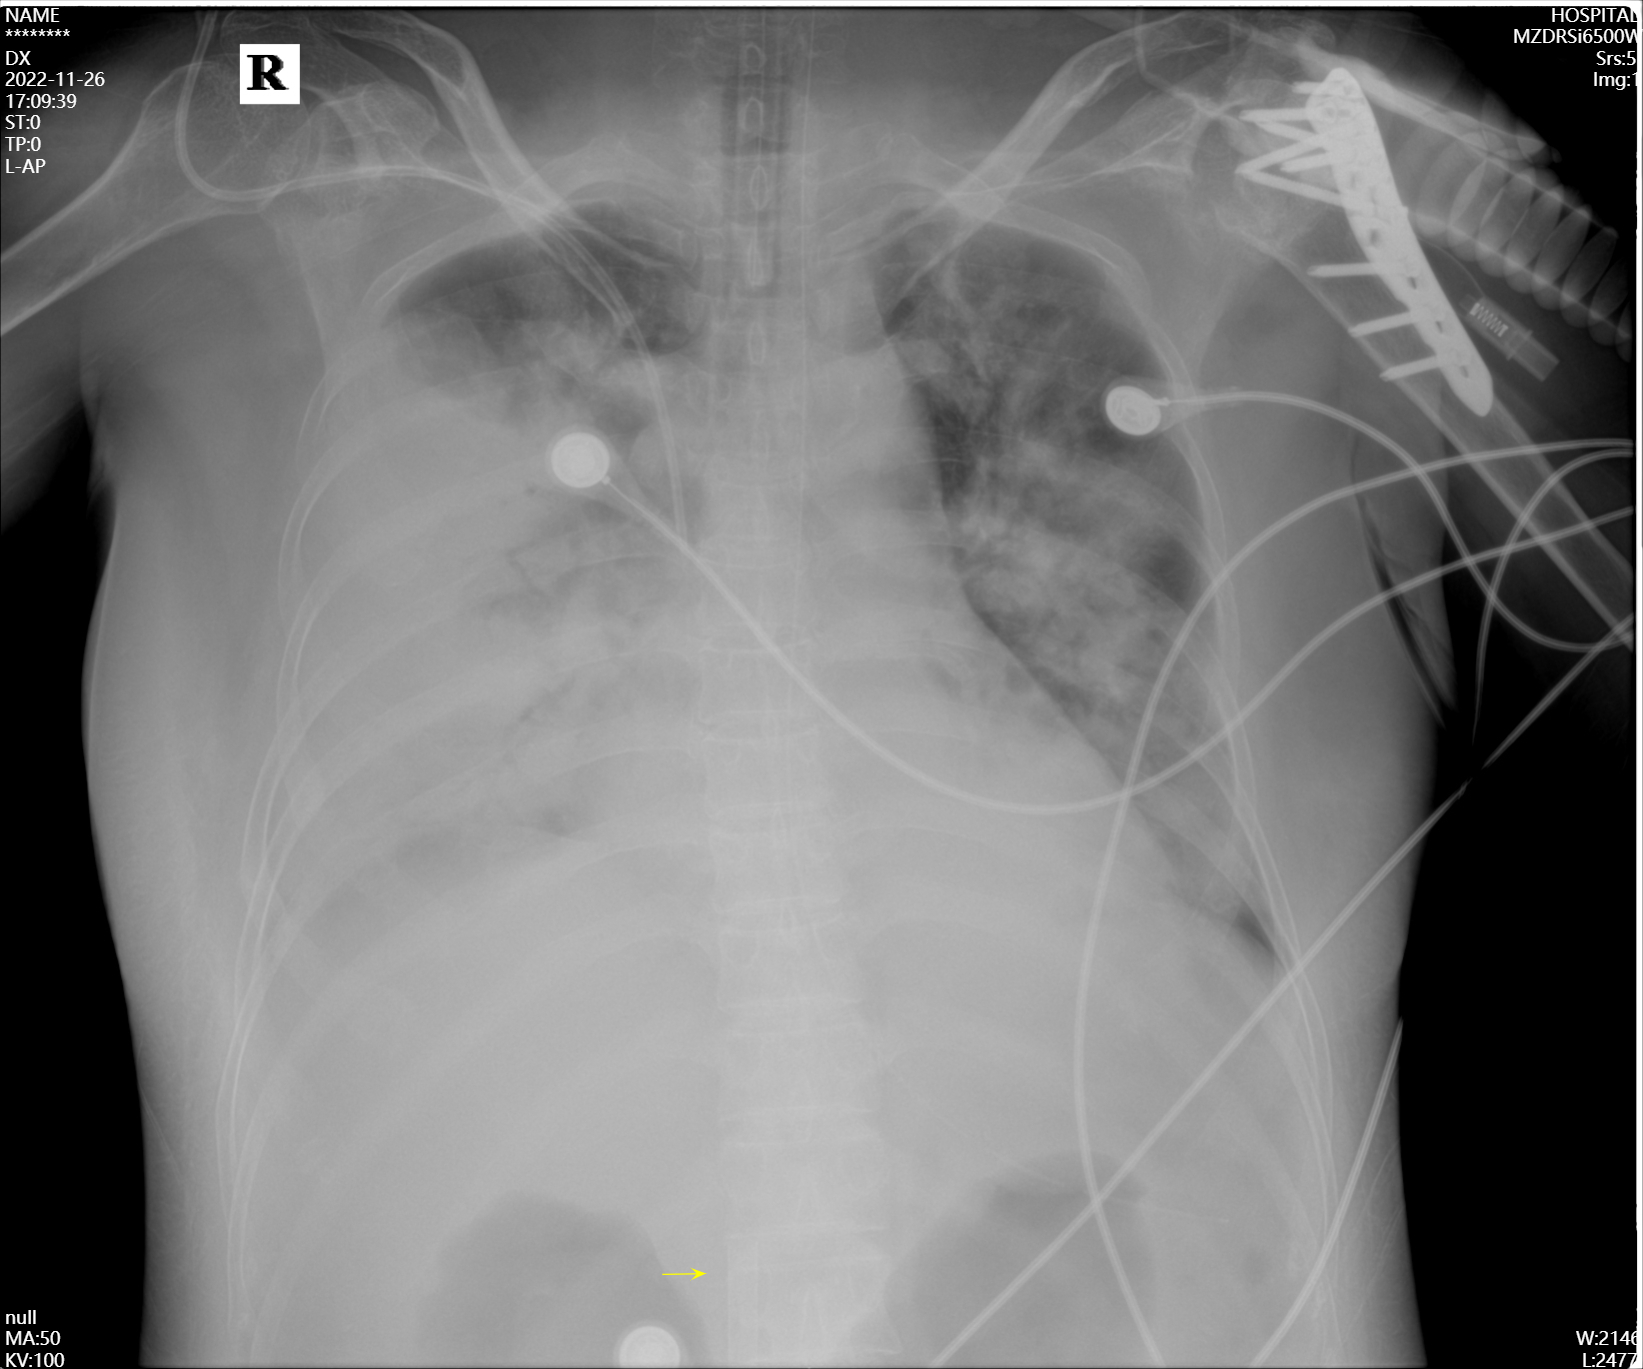

本病例报道经十堰市太和医院医学伦理委员会审核通过,审批号为:科研快审(2023KS07)号。患者女性,59岁,因“咳嗽、咳痰伴呼吸困难3 d,意识障碍10 h”入本院,急诊行气管插管、呼吸机辅助呼吸,后以“重症肺炎”收入重症医学科。既往史:2021年冠心病行支架植入术,2022年5月左侧肱骨及左侧胫骨平台骨折。体格检查:神志镇静,气管插管、呼吸机辅助呼吸(呼吸机参数:容积控制同步间歇指令通气(volume-controlled synchronized intermittent mandatory ventilation, V-SIMV),吸入氧浓度(fraction of inspired oxygen, FiO2)1.00,呼吸频率(respiratory rate, RR)20次/min,潮气量(tidal volume, VT)480 mL,呼气末正压(positive end expiratory pressure, PEEP)12 cmH2O(1 cmH2O=0.098 kPa。生命体征:体温39.8 ℃,RR 37次/min,心率154次/min,有创血压85/52 mmHg [1 mmHg=0.133 kPa,NE 1.0μg/(kg·min)],外周血氧饱和度(peripheral oxygen saturation,SpO2)83%。口唇轻度发绀,双肺呼吸音粗糙,双肺可闻及广泛痰鸣音。心音可,心率154次/min,律齐,各瓣膜未闻及病理性杂音; 腹膨隆,肝脾未及,肠鸣音弱。双下肢无水肿。辅助检查:血液分析:白细胞计数1.23×109/L,中性粒细胞百分比81.4%,血红蛋白103 g/L,血小板计数49×109/L; 降钙素原35 ng/mL; 血气分析:pH 7.28,动脉血二氧化碳分压(arterial partial pressure of carbon dioxide, PaCO2)46 mmHg,动脉血氧分压(arterial partial pressure of oxygen, PaO2)58 mmHg,HCO3- 21.6 mmol/L,实际碱剩余-4.9 mmol/L,乳酸5.4 mmol/L,血氧饱和度(oxygen saturation, SO2)85%; 脑钠肽5 745 ng/L; 肌钙蛋白-I 0.76 ng/mL; 肌酸激酶MB同工酶31.8 U/L; 心电图:窦性心动过速; 心脏彩超:射血分数60%,心脏结构、功能及血流动力学未见明显异常; 胸部CT:双肺感染性病变。初步诊断:重症肺炎、感染性休克、Ⅰ型呼吸衰竭、急性呼吸窘迫综合征(acute respiratory distress syndrome, ARDS)、冠心病支架植入术后、心功能不全、左侧肱骨骨折内固定术后(图 1)。

| 图 1 患者2022-11-26床边胸片 |